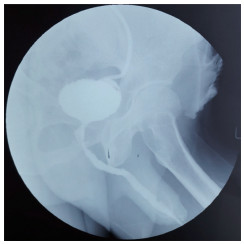

1.2 术前评估局部尿道查体观察尿道外口、阴茎头、包皮外形及阴茎段尿道海绵体是否可触及质硬瘢痕组织,见图 1。顺行或逆行尿道造影检查观察前尿道狭窄的部位和长度,如尿道外口狭窄不能行逆行造影,则仅行顺行造影,见图 2。术前均于门诊行耻骨上膀胱穿刺造瘘术。

| 图 1 LS病变累及的阴茎 Fig.1 LS involved balanus |